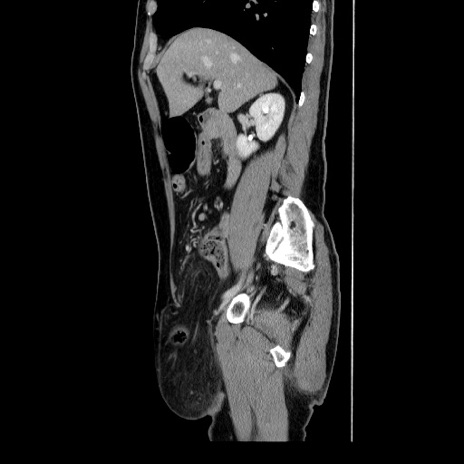

冠状断像

【症例】60歳代 男性

【主訴】右鼠径部膨隆

【現病歴】1年程前より右鼠径部膨隆あり。自己にて還納可能だったため放置していた。3時間前より右鼠径部の脱出を認め、還納困難となり受診。

【身体所見】右鼠径部に小児頭大の膨隆あり。弾性硬であり、用手還納は困難。左鼠径部にも膨隆を認める。脱出はなし。